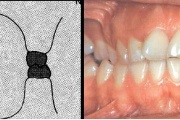

Sügav hambumus

Normaalse jäävhammaskonna pilt küljelt ja eest vaadatuna.

ülemised eeshambad katavad täielikult alumisi